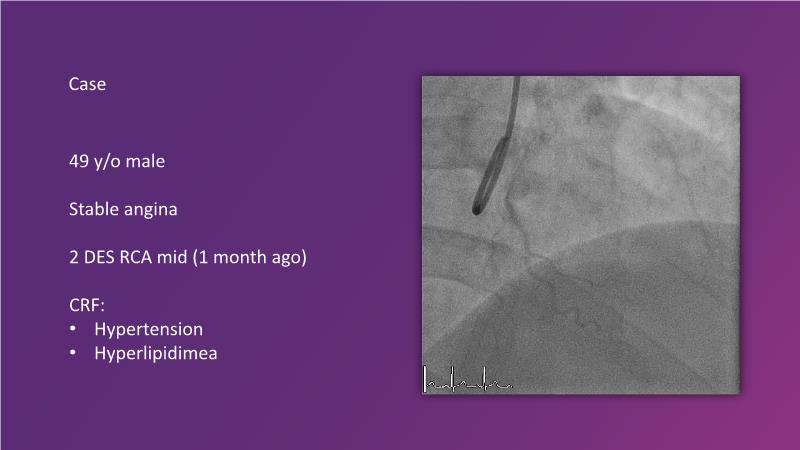

Watch this session to learn how to accurately interpret OCT-visualized dissections for an optimized PCI approach using drug-coated balloons (DCB) or drug-eluting stent (DES), to understand the critical role of sufficient and persistent sirolimus content in the vessel wall after using a sirolimus-coated balloon, to get a glimpse into the future of vulnerable plaque treatment with drug-coated balloons, and to receive the latest clinical updates on bioresorbable scaffolds with long-term follow-up.

- To learn correct interpretation of OCT visualised dissections for optimised PCI approach with drug-coated balloon or DES